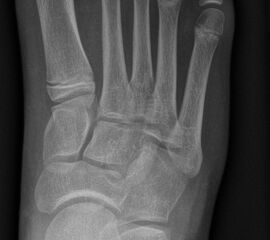

Abb. 2 a-c: offene Wachstumsfugen MT I Basis und Zehen (a), teilweise geöffnete Wachstumsfugen (b) und geschlossene Wachstumsfugen (c).

In der Regel bestehen aktive Wachstumsfugen bei Mädchen bis zum 12. und bei Jungen bis zum 14. Lebensjahr, mit Abweichungen von einem Jahr nach unten und nach oben. Präzise Informationen unter anderem darüber gibt das präoperative Röntgenbild (Abb. 2).